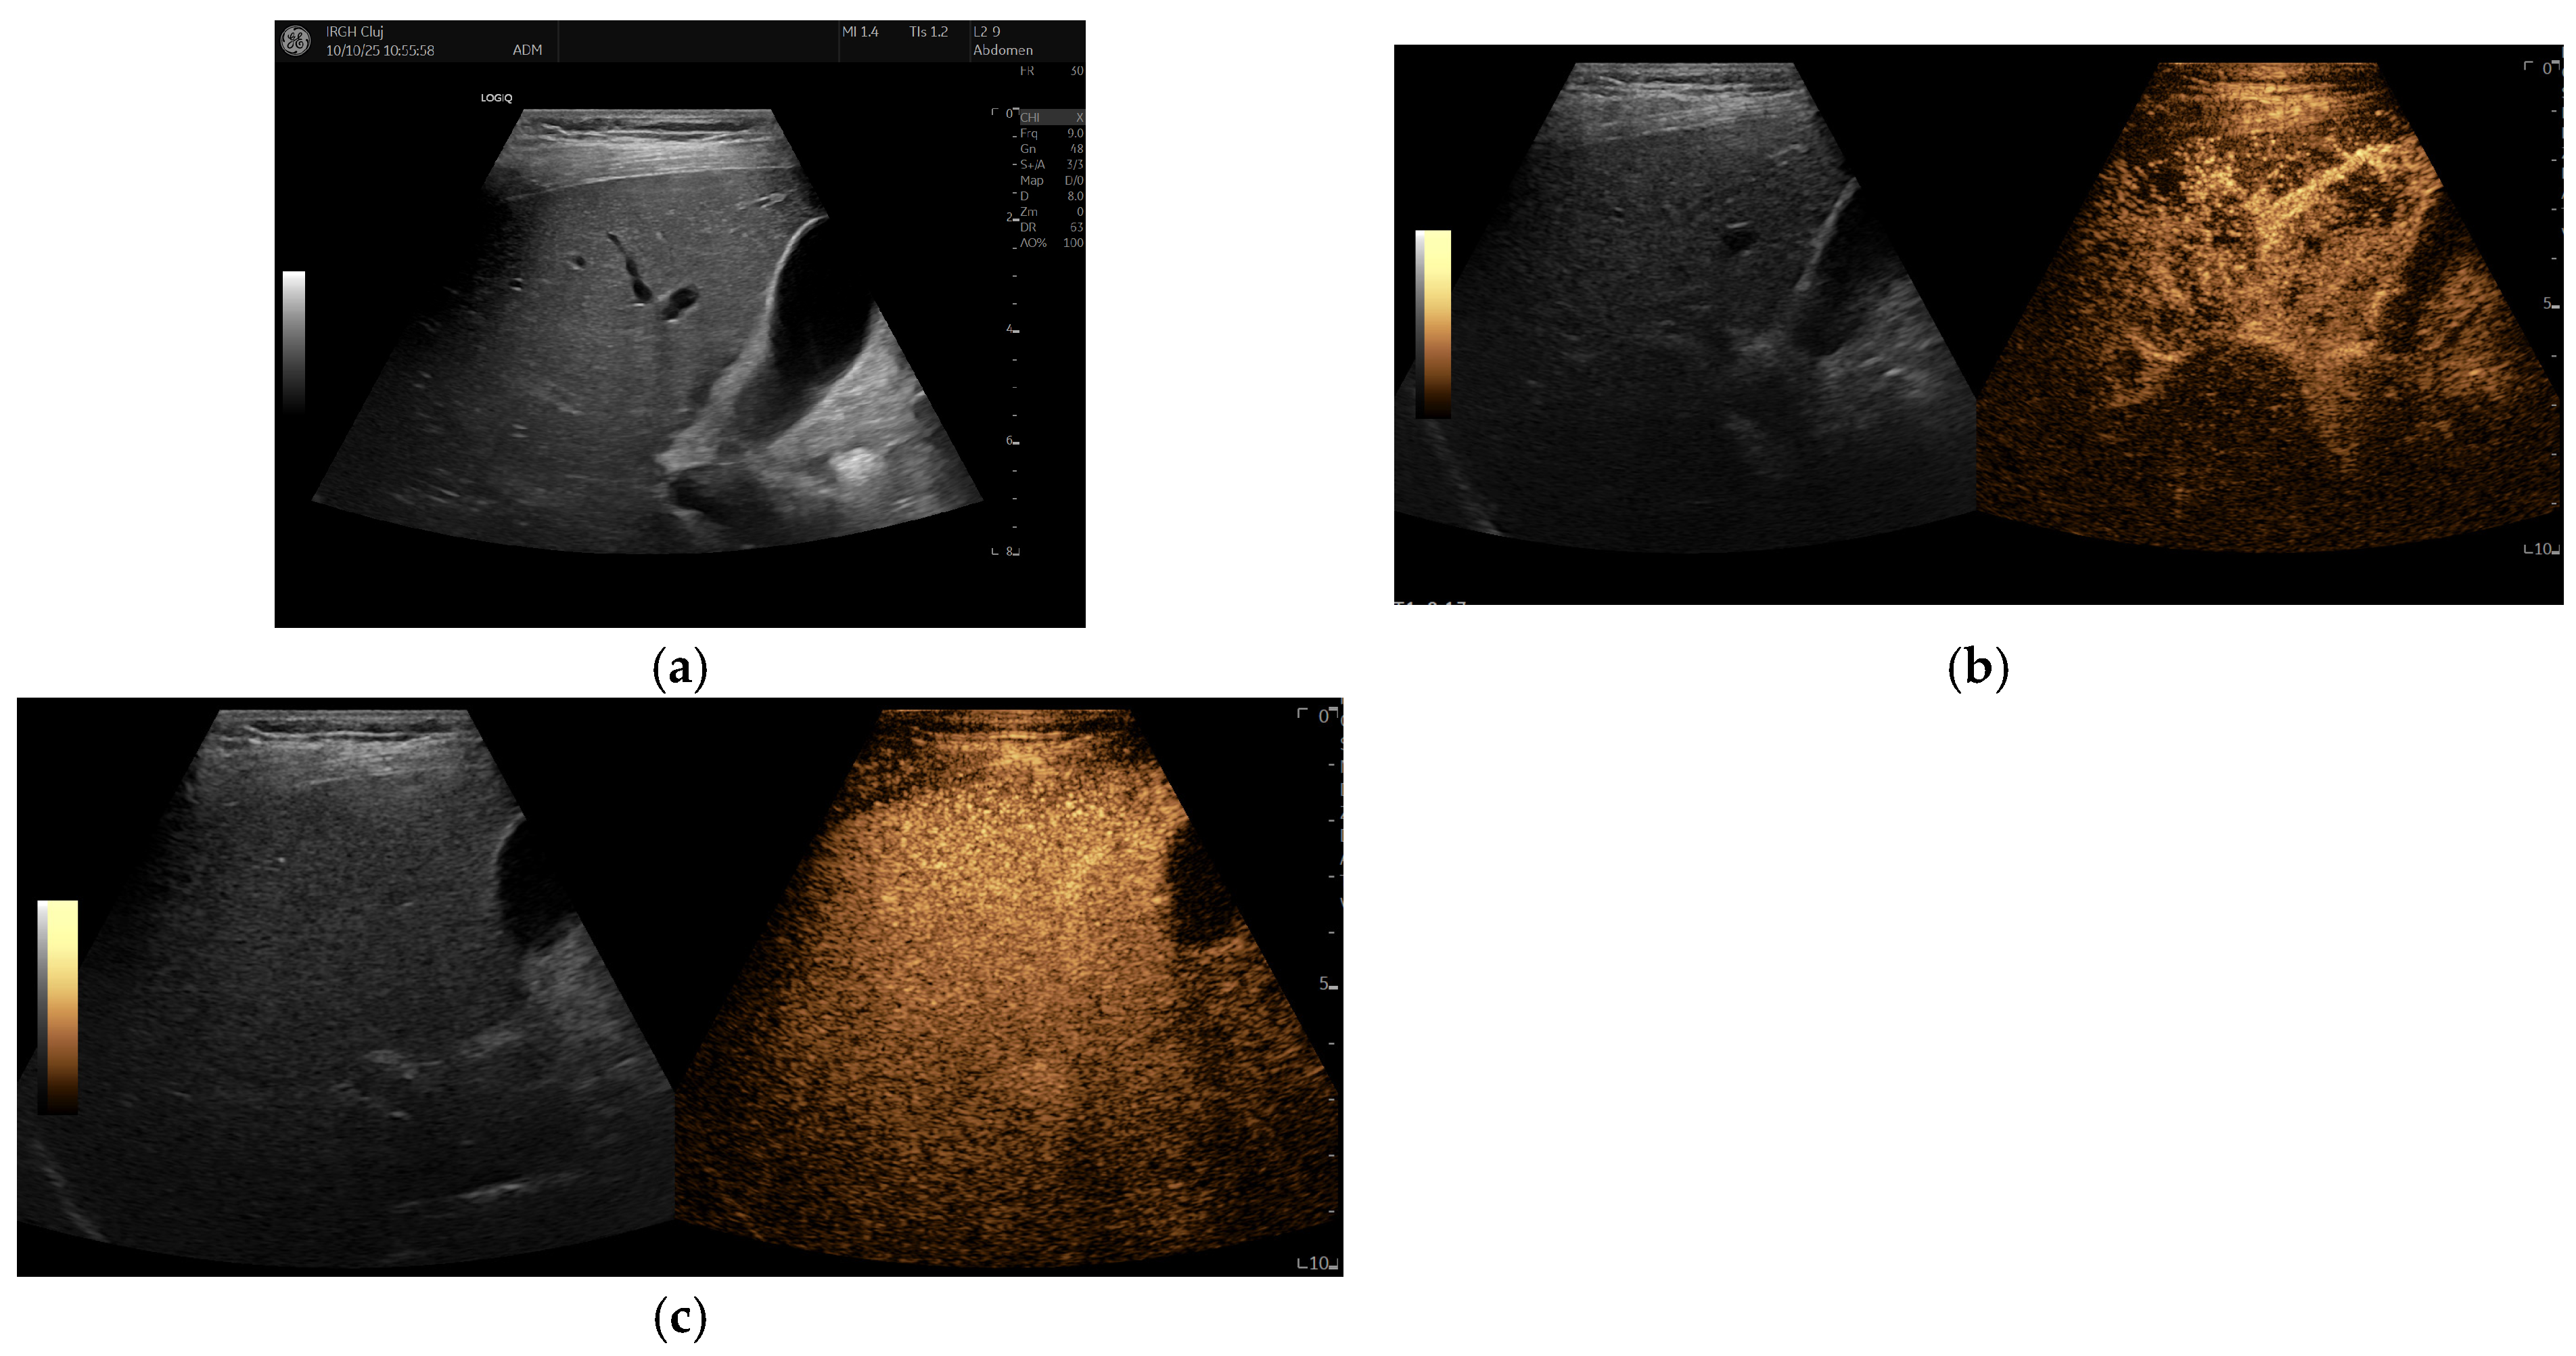

Remarkably, under anti-TNF treatment, there has been a significant improvement in liver lesions, as evidenced by reductions in both their size and number on repeated liver imaging (Figure 3 and Figure 4), along with normalisation of GGT levels in subsequent years. Improvement was evident after just one year of treatment and continued to progress until the patient reached 17 years of age. Splenomegaly persisted without evidence of portal hypertension, and liver stiffness on elastography decreased slightly over time (6.1 kPa before Etanercept and 5.6 kPa after treatment).

In our patient, the FNH-like lesions showed an early positive response after starting Etanercept, with a noticeable decrease in both the size and number of nodules. This improvement was maintained, as imaging performed nine years into continuous anti-TNF therapy showed substantial regression of the hepatic nodules. To our knowledge, this is the first documented case of FNH-like liver lesions in DADA2 that show long-term improvement with anti-TNF treatment.

Figure 4. Subsequent MRI examinations after 5 years (a,c) and 9 years (b,d) of Etanercept treatment since the initial assessment. Gd-enhanced fat-saturated T1-weighted images in the arterial (a,b) and late (c,d) phases. Only one lesion (arrow) remains visible, showing hyperenhancement in the periphery and a central scar with progressive, incomplete filling in the late phases. The lesion has shrunk in the last examination.